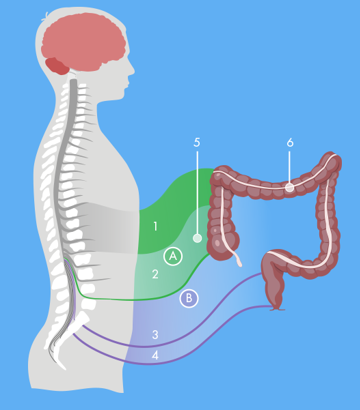

Die neurogene Blase ist eine Erkrankung des unteren Harntrakts, die durch Schädigungen oder Erkrankungen des Nervensystems verursacht wird.

Der absteigende Dickdarm und das Rektum sind das letzte Stadium des menschlichen Darmsystems. Normalerweise ist der Enddarm relativ leer. Der Stuhl tritt nicht kontinuierlich in den Enddarm ein, sondern als Massenbewegung

Dieser Artikel bietet einen guten Einstieg in das Thema „Darm“ inklusive Überblick über die Funktion des Verdauungssystems, die beteiligten Organe und die neurologische Steuerung.

Darmfunktionsstörungen können verschiedene Ursachen haben. In Betracht kommen neurologische Erkrankungen, bei denen die Weiterleitung von für die Darmfunktion wichtigen Nervenreizen beeinträchtigt ist, oder auch eine Obstruktion. In manchen Fällen kann keine medizinische Ursache für die Funktionsbeeinträchtigung gefunden werden.

Die meisten Querschnittgelähmten zeigen deutliche Symptome einer neurogenen Darmfunktionsstörung, wie z. B. Verstopfung (42% der Betroffenen) und Stuhlinkontinenz (bis zu 77% der Betroffenen).